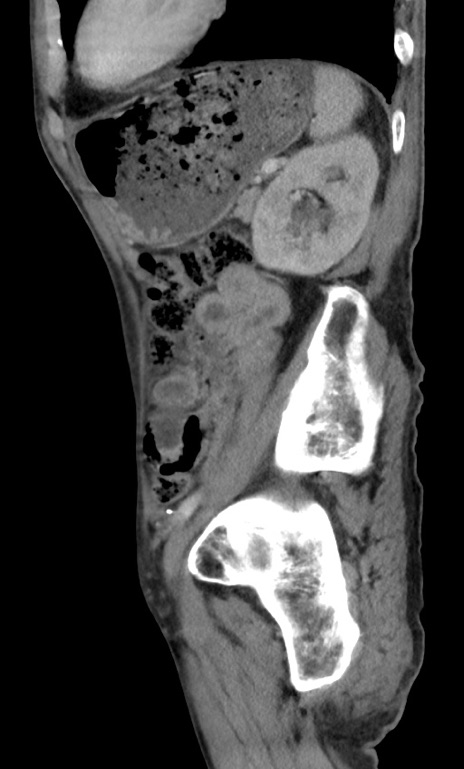

横断像

【症例】 70歳代男性

【主訴】右鼠径部腫瘤、疼痛

【現病歴】本日朝より上記主訴あり、受診。

【既往歴】膀胱癌にて膀胱全摘、両側尿管皮膚瘻

【データ】WBC 5600、CRP 0.56